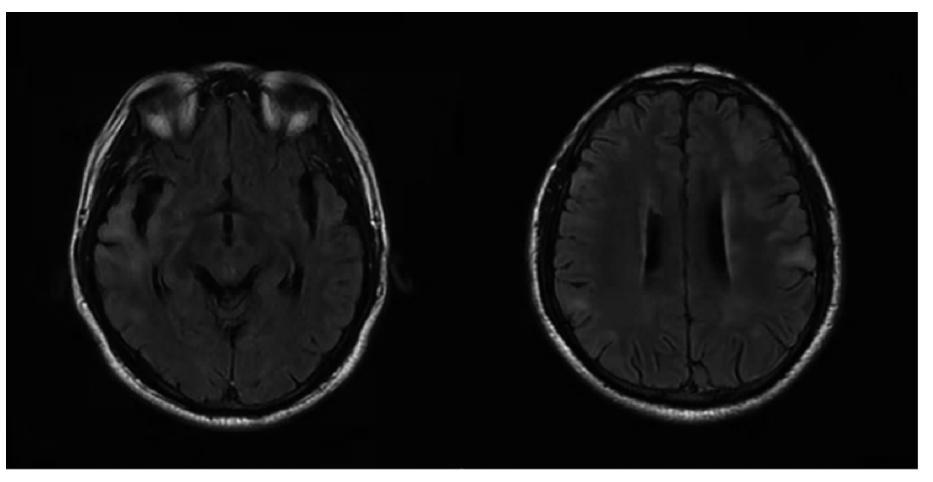

• 磁敏感加权成像黑质“燕尾征”在帕金森病中的诊断价值

2021, 46(7):823-827. DOI: 10.13406/j.cnki.cyxb.002859

摘要 (186) HTML (257) PDF 1.23 M (204) 评论 (0) 收藏

摘要:目的: 探讨3.0 T磁敏感加权成像(susceptibility weighted imaging,SWI)中“燕尾征”缺失在帕金森病(Parkinson's disease,PD)的诊断价值并分析黑质小体-1(nigrosome-1)可视化与PD患者临床资料的相关性。 方法: 收集2017年9月至2019年11月于重庆医科大学附属第一医院神经内科住院的50例PD患者及年龄、性别与之匹配的57例非PD患者。所有受试者均接受3.0 T头颅SWI检查。在获得的SWI图像上,由2名临床医师采用盲法独立对双侧“燕尾征”进行评估。一侧“燕尾征”缺失即判定为PD。计算“燕尾征”缺失诊断PD的灵敏度、特异度、预测值和准确度,并分析nigrosome-1可视化与PD患者临床资料的相关性。 结果: 以临床诊断作为金标准,45例PD患者判断正确,评估者之间的一致性很高(k=0.963,P=0.000)。“燕尾征”缺失诊断PD的灵敏度为90.0%,特异度为91.2%,阳性预测值为90.0%,阴性预测值为91.2%,准确度为90.7%。44例PD患者临床症状不对称,其中32例患者nigrosome-1可视化不对称。PD患者nigrosome-1可视化偏侧和临床症状偏侧比较差异无统计学意义(χ2=5.756,P=0.056)。11例PD患者双侧nigrosome-1全部缺失,纳入全部缺失组,其余PD患者为非全部缺失组。全部缺失组和非全部缺失组患者的汉密尔顿抑郁量表评分差异有统计学意义(U=126.500,P=0.038),而病程、帕金森病统一评定量表第Ⅲ部分、改良Hoehn-Yahr(H-Y)分级、简易智能状态量表和蒙特利尔认知评估量表评分差异均无统计学意义(P=0.768、0.140、0.839、0.054、0.067)。 结论: “燕尾征”缺失诊断PD的准确率较高,缺失程度可能与PD患者的抑郁程度有关,对PD的诊断有一定参考价值。